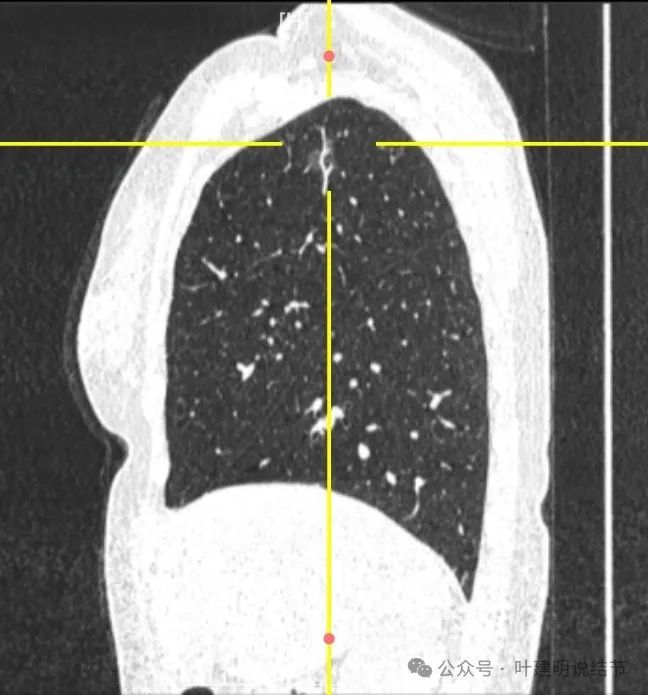

2024年9月病灶仍在,实性成分较前略显明显,矢状位清楚显示穿行血管壁毛糙。冠状位显示分叶以及病灶与血管间没有间隙。